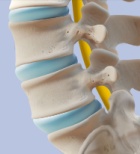

מחקר מוכיח: אובדן גובה בגיל מבוגר נובע לעתים משבר בחוליות...

אוסטאוארתריטיס נקראת גם מחלת מפרקים ניוונית,זוהי מחלת מפרקים כרונית הניכרת בהתנוונות (חיספוס וחירור) של הסחוס בתוך מפרק, הסיבה למחלה באוכלוסיה המבוגרת אינה ידועה והיא נפוצה עד כדי כך שחלק מהרופאים מתייחסים אליה כחלק מתהליך ההזדקנות, למרות שאין זה כך.היא מתאפיינת באיבוד מתקדם של הסחוס שבתוך המיפרק וביצירת עצם חדשה סביב המיפרק הנגוע. בנוסף לכך ישנה דלקת קלה של הסינובית (המעטפה הדקה העוטפת את המיפרק). החולה סובל מכאבים המתגברים בשעת פעולה ומוקלים במנוחה. המיפרק נעשה גדול יותר, התנועה שלו מוגבלת וקיימת ירידה ביכולת של החולה לבצע פעולות שונות (כמו הליכה). באופן משני מתנוונים השרירים סביב המיפרק הנגוע מחמת תפקוד מוגבל של השרירים. המחלה נפוצה מאוד בקרב מבוגרים וקשישים. נמצא כי אצל 80% מהאוכלוסיה מגיל 75 ומעלה ישנה עדות רנטגנית לפגיעתה של המחלה. אוסטיאוארתריטיס הוא הגורם הראשון במעלה להגבלה בכושר הפעולה. הגיל הוא גורם סיכון למחלה זו - ככל שהאדם מבוגר יותר, הסיכוי שלו לחלות במחלה גבוה יותר. המחלה המתוארת לעיל היא המחלה הראשונית וסיבתה לא ידועה יתכן גם אוסטאוארטריטיס שניוני על רקע מחלה זיהום ,פציעה או שימוש מופרז במפרק. הטיפול היעיל בדרך כלל הוא התעמלות חימום ופיזיותרפיה בשילוב עם מנוחה כאשר המפרקים כואבים.